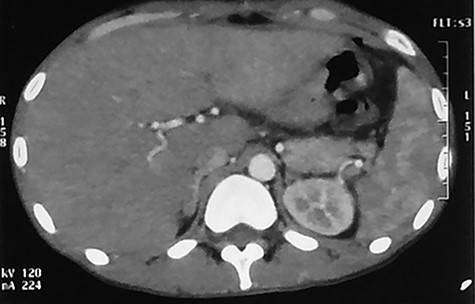

Abdominal CT scan at 3 months showed disappearance of the miliary abscess and also of the hepatomegaly (Fig. 2).

Abdominal CT scan (arterial phase) performed at 90th day after the beginning of the antibiotherapy showing normal liver parenchyma.